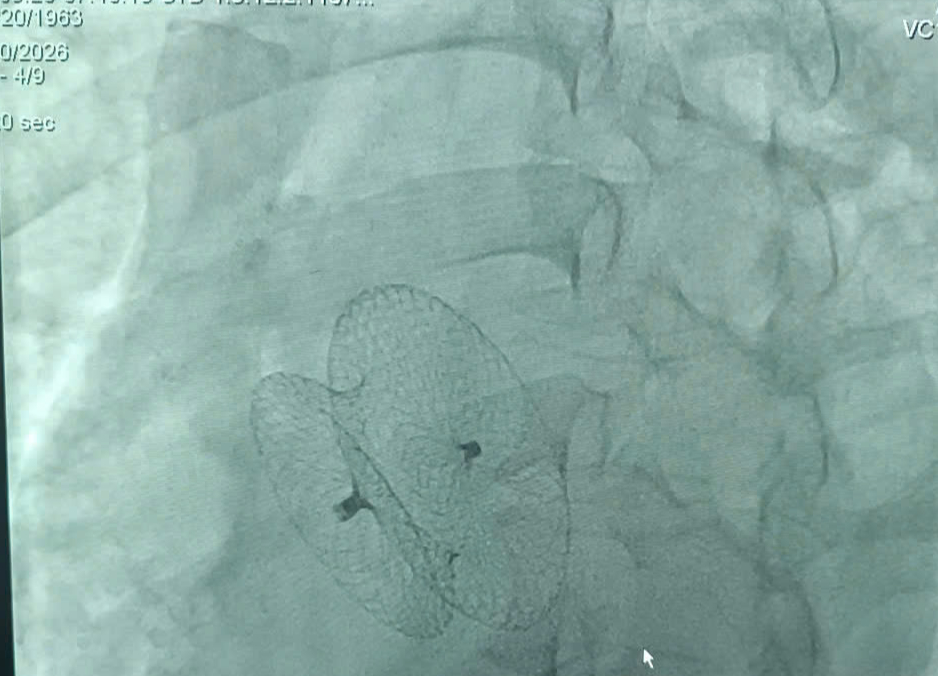

Hồi hộp, tim đập nhanh kéo dài, phát hiện bệnh tim nguy hiểm - Ảnh 2.

Bệnh nhân được can thiệp bít lỗ thông liên nhĩ